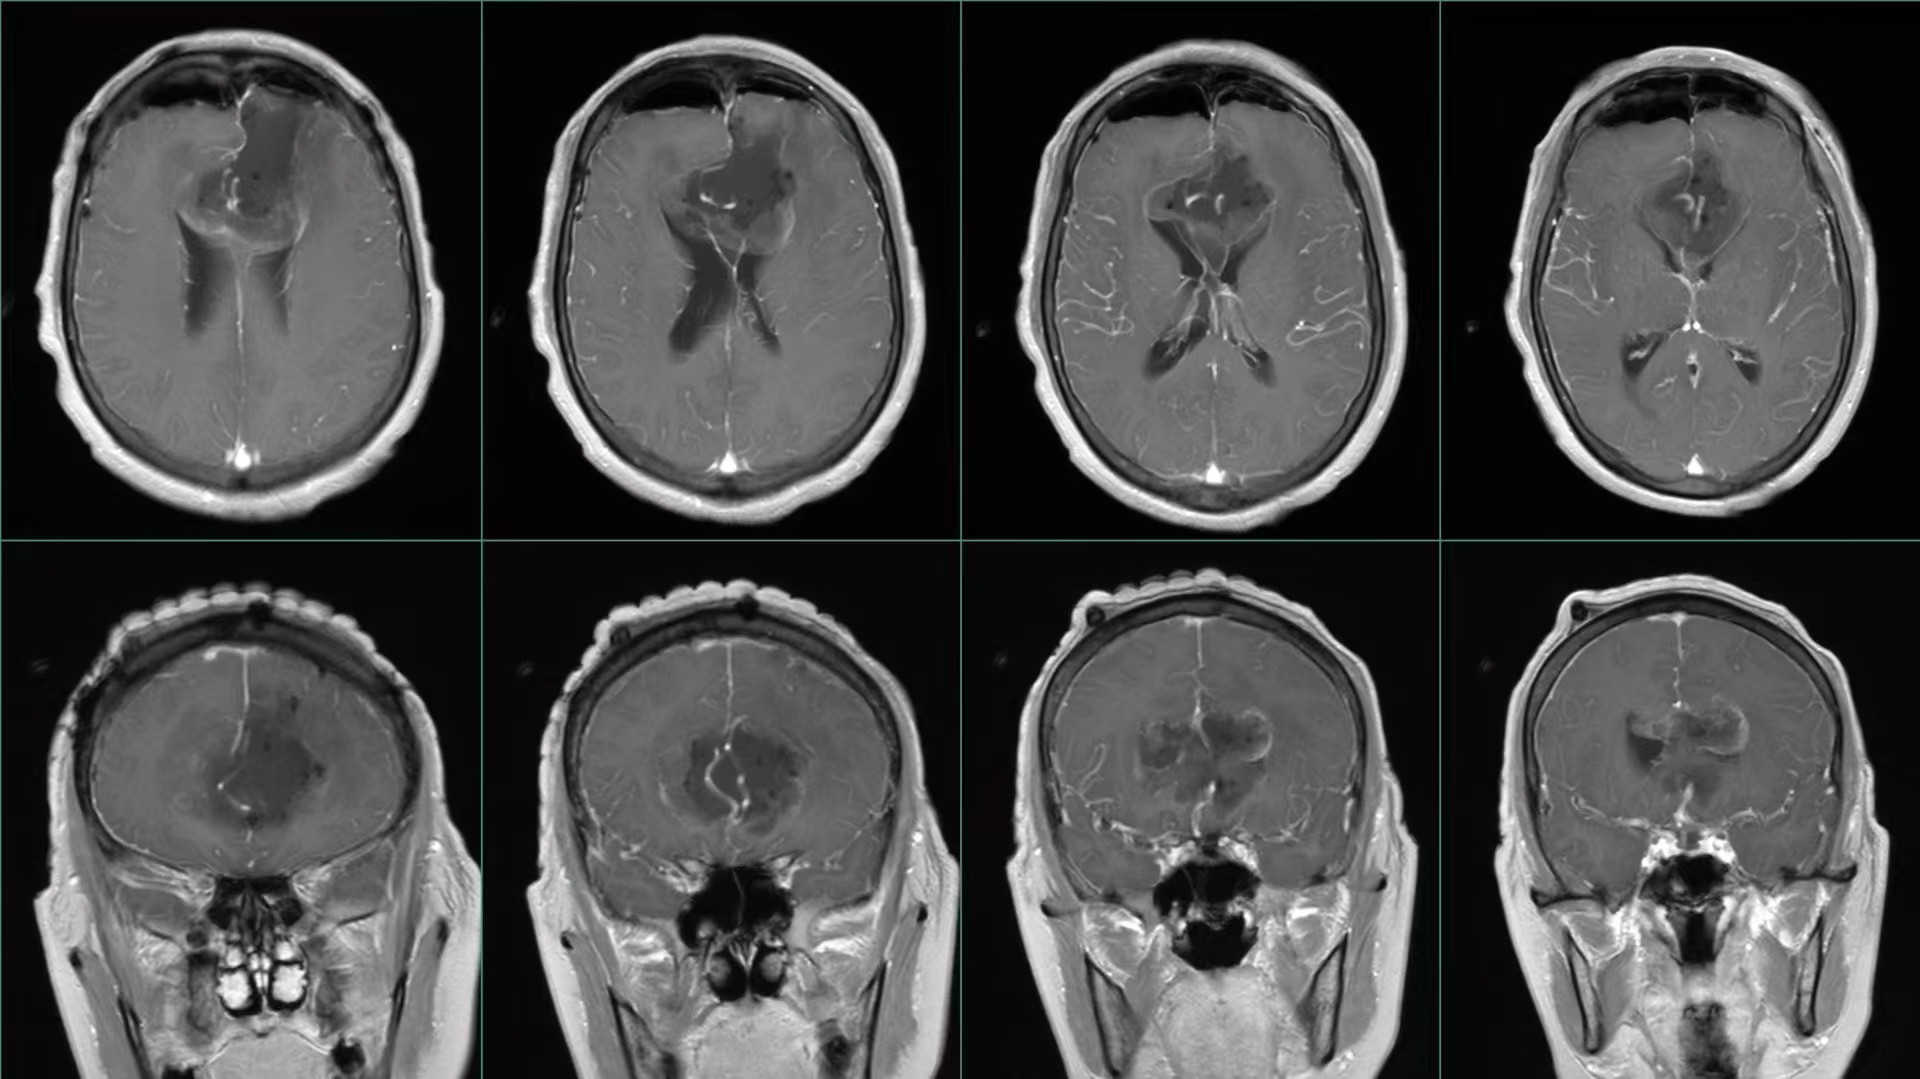

巨大蝴蝶型胶质母细胞瘤(Butterfly glioblastomas)切除术

患者,女性,58岁,因“反应迟钝、记忆力下降1月,加重伴头痛、恶心、呕吐1周”入院。